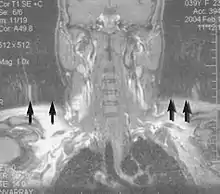

Motion artifact (T1 coronal study of cervical vertebrae)[117]

An MRI artifact is a visual artifact, that is, an anomaly during visual representation. Many different artifacts can occur during magnetic resonance imaging (MRI), some affecting the diagnostic quality, while others may be confused with pathology. Artifacts can be classified as patient-related, signal processing-dependent and hardware (machine)-related.[117]